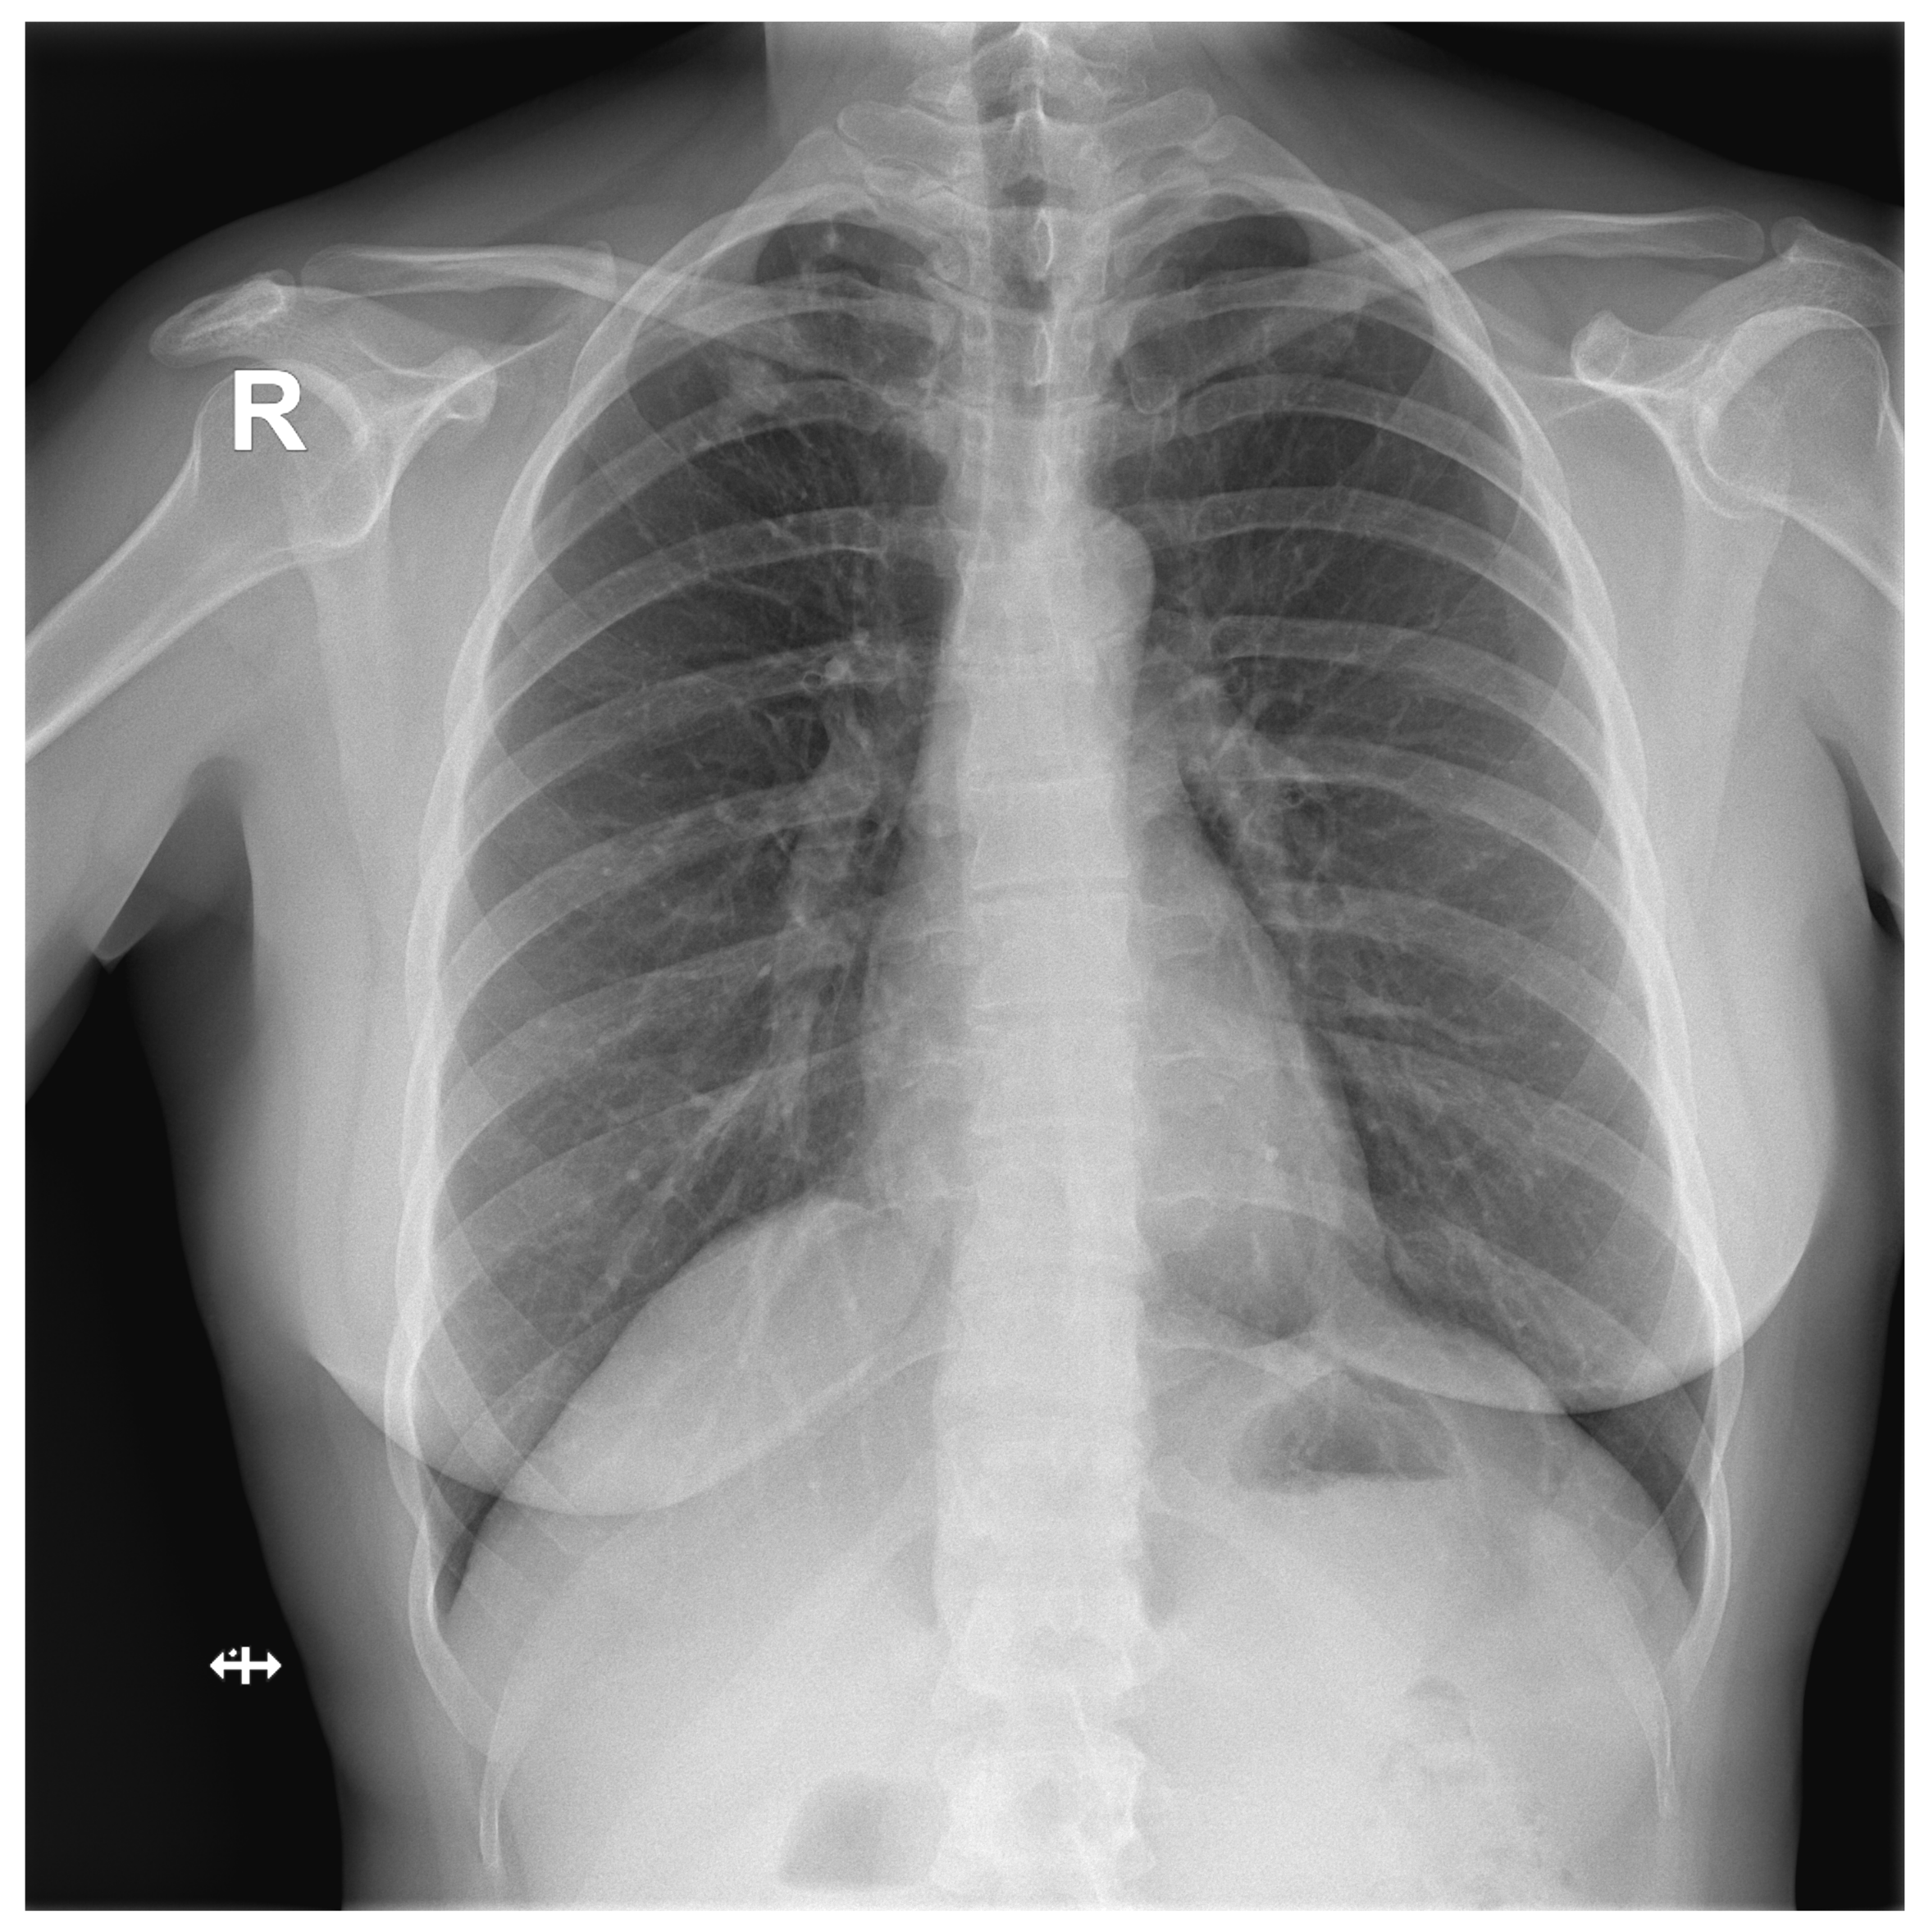

A total of 127 images with established ground truth were evaluated: 40 (31.5%) with a finding and 87 (68.5%) without any finding. The DLAD correctly identified 37 images as abnormal and 56 images as normal (73.2% in total). A total of 31 (24.4%) normal images were incorrectly classified as abnormal. The higher false positive rate was expected since DLAD was trained to assign even suspect findings as abnormal. Another three (2.4%, Figure A2, Figure A3, Figure A4) images were incorrectly classified as without any finding, even though they were with findings (false negative rate) (Table 3).

Figure A3.

False Negative image #2 incorrectly classified by DLAD software during the retrospective study. The software failed to detect a lesion in lung parenchyma. Assessed radiologists #5f0, #442 and #c8a also incorrectly classified this image as Normal.